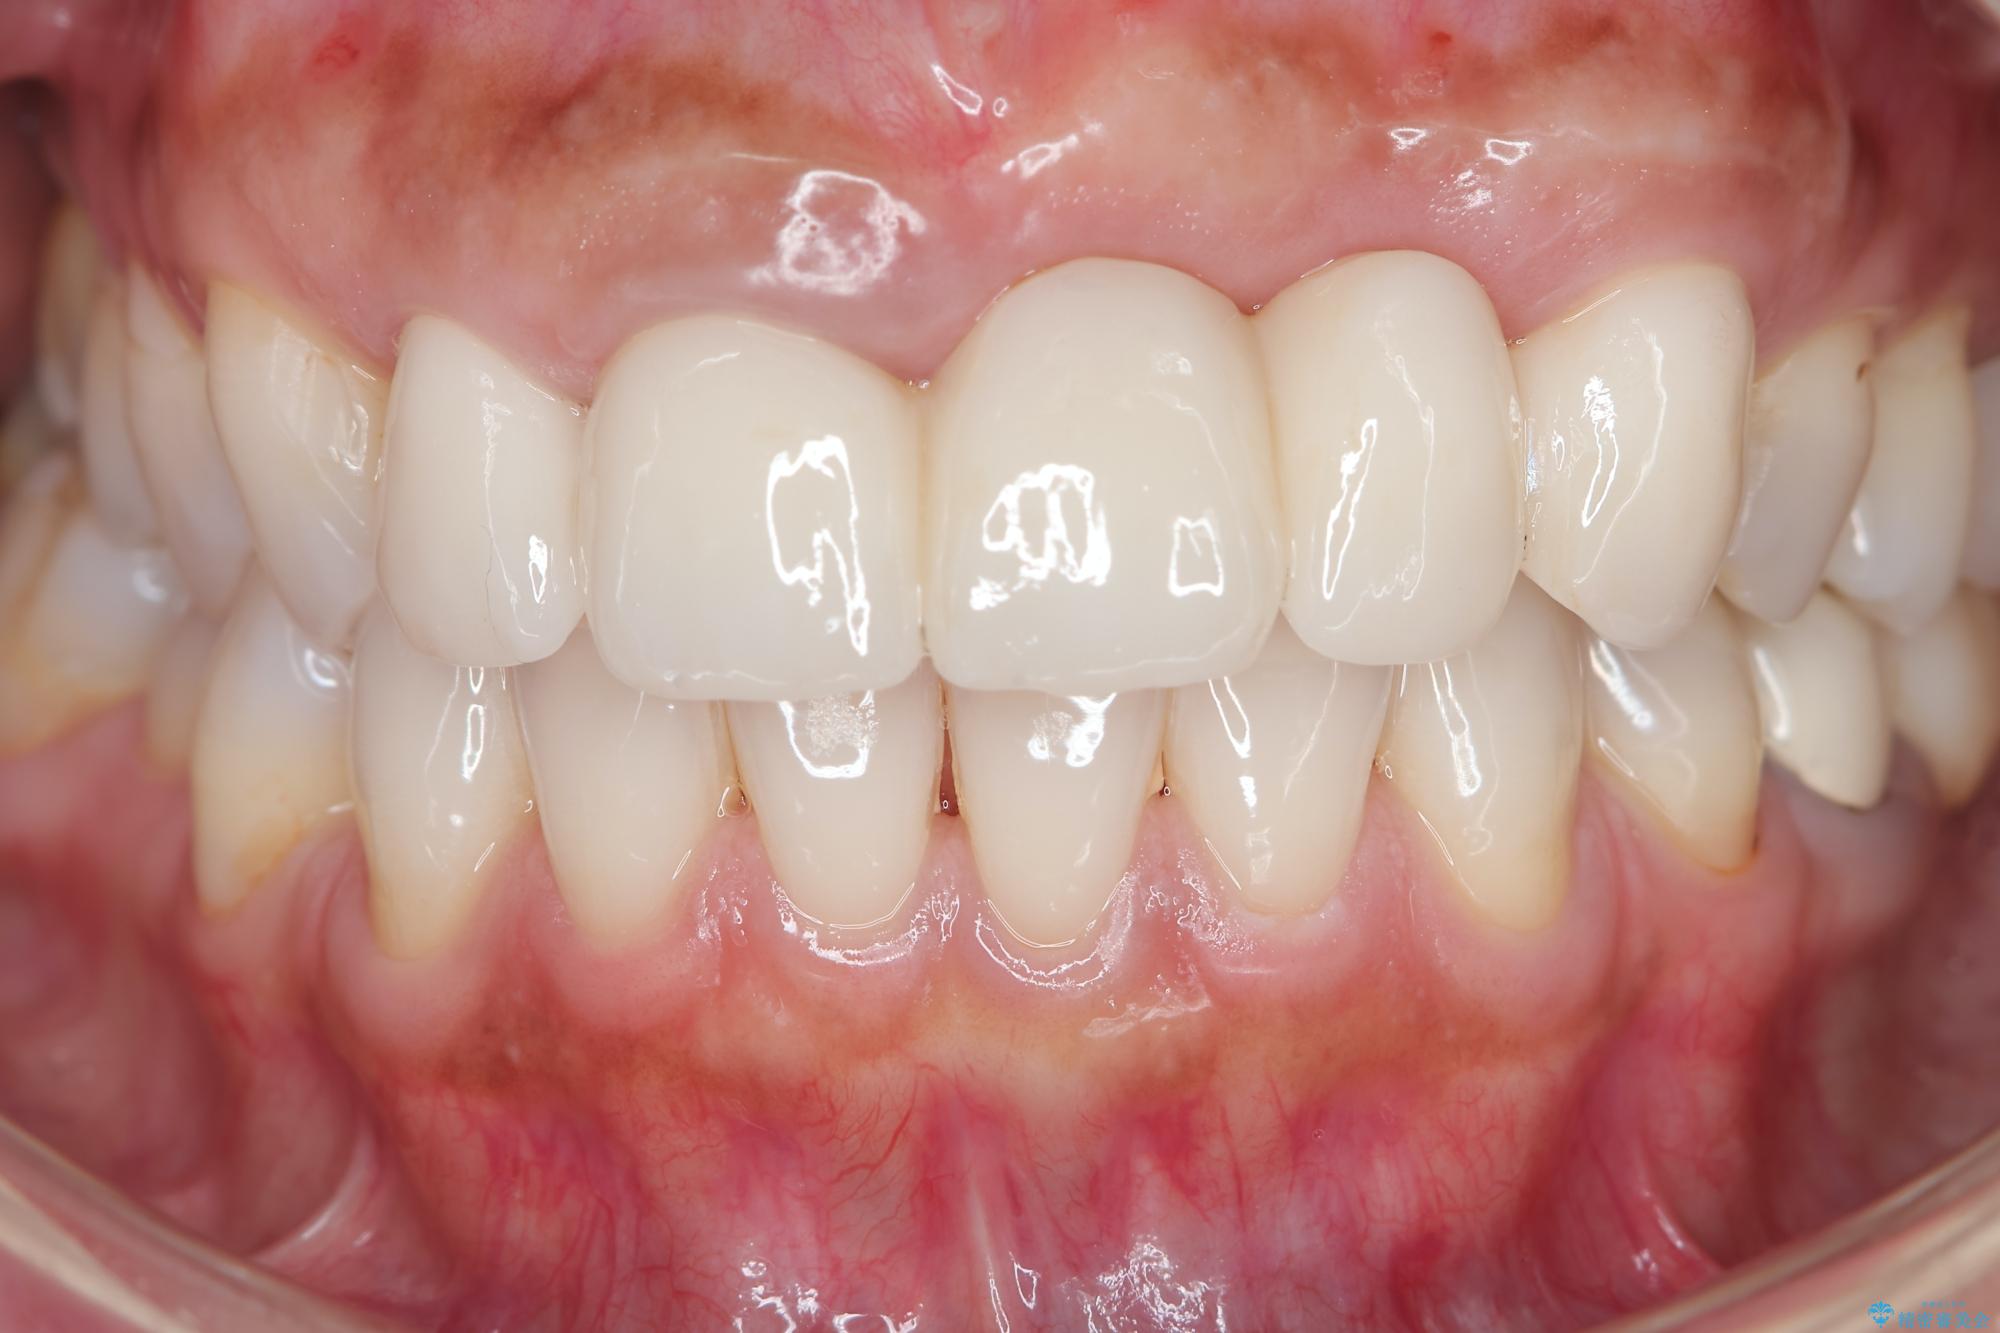

治療を終えて

一件綺麗に見えるセラミックも適合や精度が悪いと、内部で虫歯が進行し亀裂や破折、悪臭の原因となることがあります。

歯槽堤保存術を併用したブリッジ治療 治療後画像 歯槽堤保存術を併用したブリッジ治療 治療後画像 歯槽堤保存術を併用したブリッジ治療 治療後画像 歯槽堤保存術を併用したブリッジ治療 治療後画像 歯槽堤保存術を併用したブリッジ治療 治療後画像 歯槽堤保存術を併用したブリッジ治療 治療後画像 歯槽堤保存術を併用したブリッジ治療 治療後画像